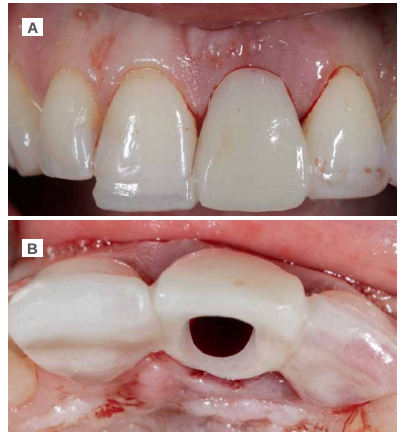

En la región del ICSI, se puede observar una mucosa eritematosa, que se acompaña de la inflamación de la región apical del diente a nivel de la encía insertada y que puede tratarse de un absceso periapical derivado de la infección de dicho diente (Figura 1). El ICSI presenta gran movilidad debido a una fractura radicular que no se puede observar a la exploración clínica.

Bajo anestesia local (articaína 4% 1:100000 adrenalina) con técnica infiltrativa a nivel del fondo de vestíbulo de la región anterior del maxilar (nervio alveolar superior anterior) y región palatina (nervio nasopalatino), se procedió a la extracción del fragmento coronal del ICSI para, posteriormente, llevar a cabo la exodoncia de la raíz del mismo (Figura 3 A). Para ello, se realizó una sindesmotomía del tejido blando circundante que permitió conocer el estado por palpación de la cortical vestibular. Tras ello, se procedió a la extracción de la raíz de forma controlada y mínimamente traumática, con una primera luxación de la misma con un botador y posterior prensión controlada con un fórceps (Figura 3B).